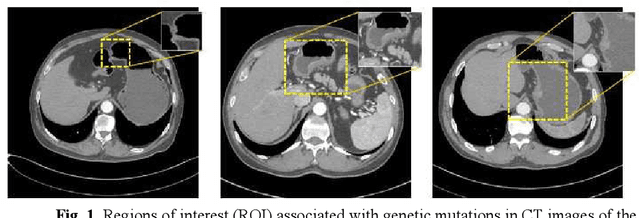

Predicting the mutation status of genes in tumors is of great clinical significance. Recent studies have suggested that certain mutations may be noninvasively predicted by studying image features of the tumors from Computed Tomography (CT) data. Currently, this kind of image feature identification method mainly relies on manual processing to extract generalized image features alone or machine processing without considering the morphological differences of the tumor itself, which makes it difficult to achieve further breakthroughs. In this paper, we propose a pyramid focusing network (PFNet) for mutation prediction and classification based on CT images. Firstly, we use Space Pyramid Pooling to collect semantic cues in feature maps from multiple scales according to the observation that the shape and size of the tumors are varied.Secondly, we improve the loss function based on the consideration that the features required for proper mutation detection are often not obvious in cross-sections of tumor edges, which raises more attention to these hard examples in the network. Finally, we devise a training scheme based on data augmentation to enhance the generalization ability of networks. Extensively verified on clinical gastric CT datasets of 20 testing volumes with 63648 CT images, our method achieves the accuracy of 94.90% in predicting the HER-2 genes mutation status of at the CT image.